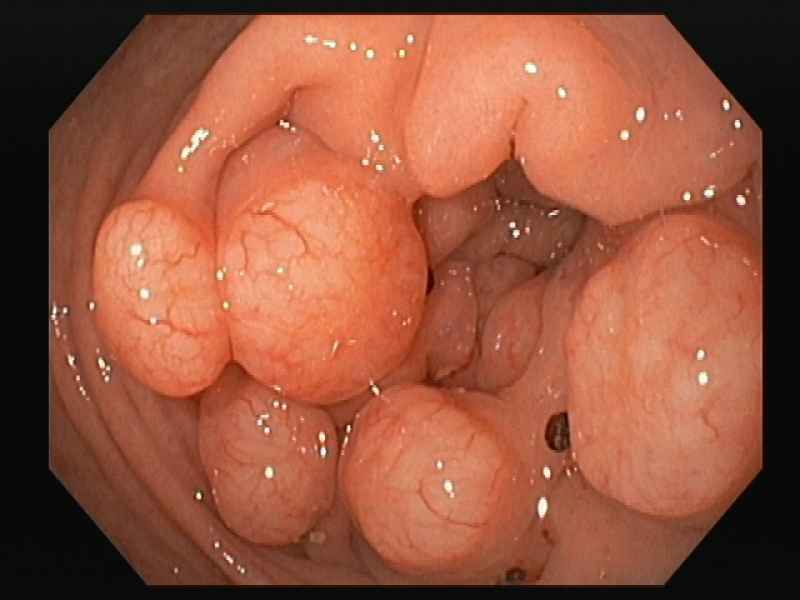

An uncommon diagnosis done by colonoscopy

Colocolic intussusception